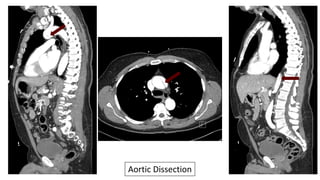

51 Year-Old With

Burning Chest Pain

For 1 Hour After

Getting In To An

Argument.

HR 57, BP 196/100

During His ED Stay

The Pain Migrates

To His Abdomen…

Aortic Dissection